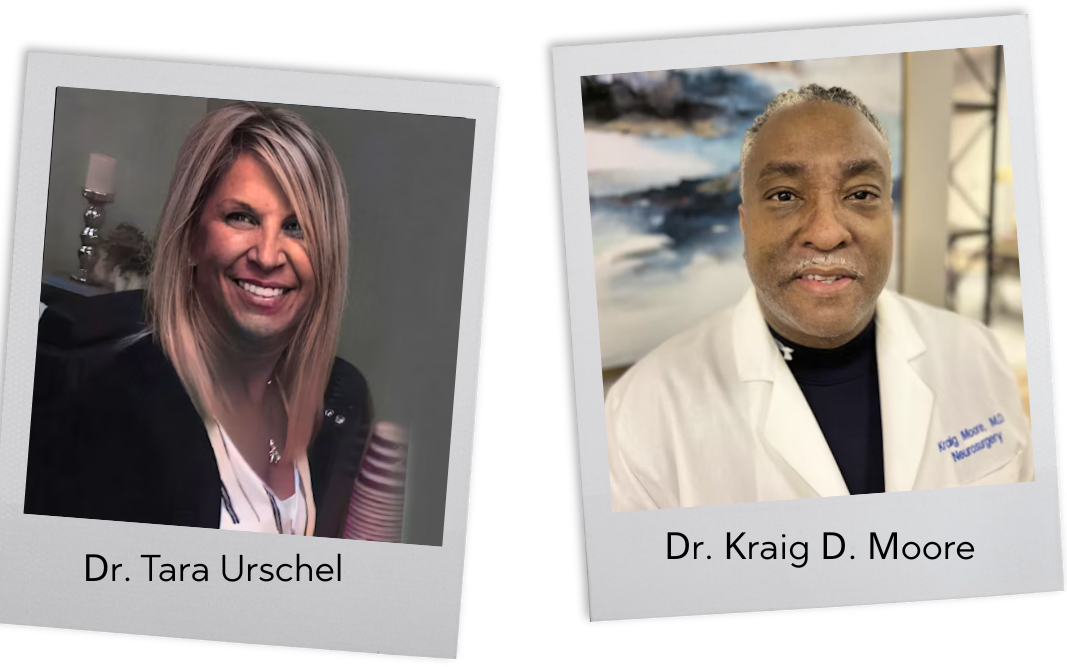

Dr. Tara Urschel is a leading provider of chiropractic care in and around Ashburn, VA. At Jaxsens Wellness Center , Dr. Urschel provides many services to her patients including services such as stress management, fibromyalgia treatments, physical therapy, and treatment for back pain, along with various other services.

Dr. Kraig D. Moore began his Medical education at The George Washington University School of Medicine and Health Sciences, where he obtained a Degree in Medicine in 1992. Following graduation, he completed his internship in General Surgery at The Washington Hospital Center in Washington, D.C. He went on to an IRTA Fellowship at The National Institute of Mental Health of the NIH where he performed Investigations in Neural Transplantation for Parkinson’s Disease as well as Investigations in Pediatric Brain Tumors.